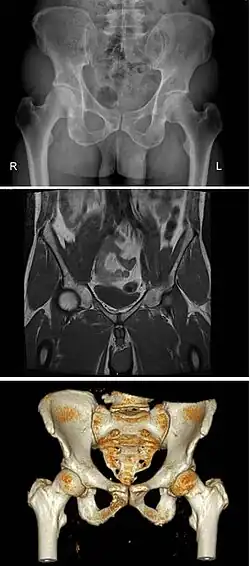

The same human pelvis, front imaged by X-ray (top), magnetic resonance imaging (middle), and 3-dimensional computed tomography (bottom)